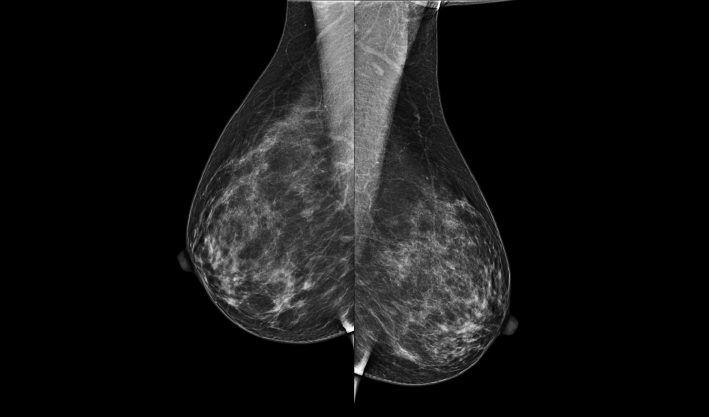

致力于致密乳腺的早期癌變篩查和微鈣化簇精準定性。